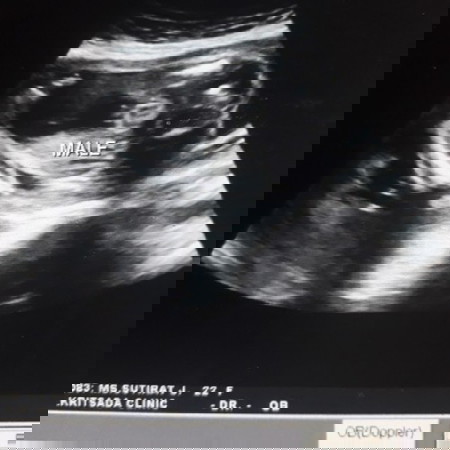

แบบนี้ได้หญิงหรือชายคะ

ชายค่ะในรูประบุชัดเจน รูปซาวน์เห็นไข่และจู๋ที่แหลมๆออกมาชัดเจน